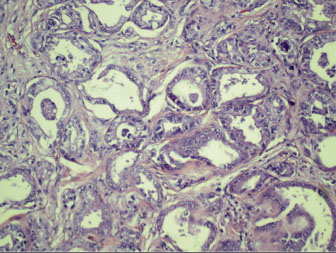

LM: Mesangial expansion, GBM thickening, nodular glomerulosclerosis (Kimmelstiel-Wilson nodules)

- hyaline caps seen as hyalinosis in the glomerulus, aka capsular drops when on the inner surface of Bowman's capsule; arterioles usually have lots of hyalinosis as well

- arteriolosclerosis - hyaline thickening or insudates in arterioles (afferent and efferent) accompanied by insudates in capillary loops (fibrin caps) and Bowman's capsule (capsular drops)

EM: thickened BM usually first sign of DM; also expanded mesangium